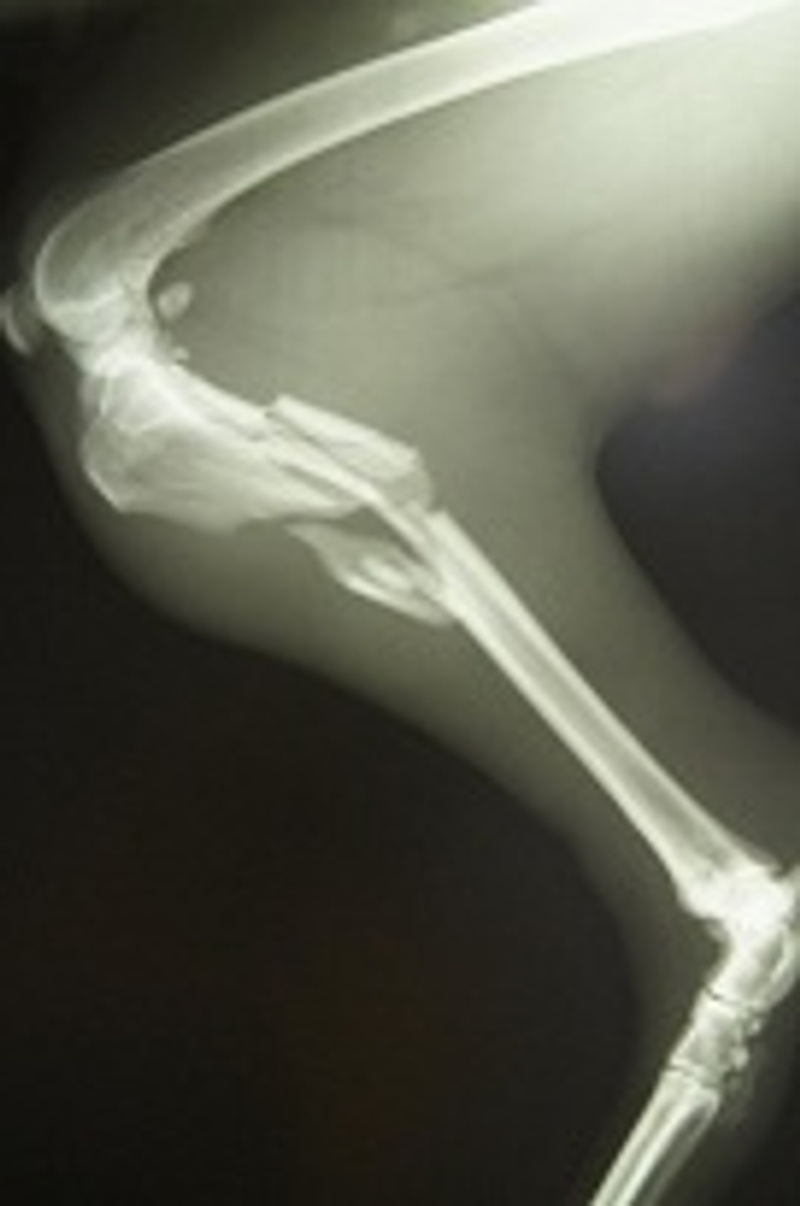

) А именно: Наталье Владимировне-оперирующему доктору